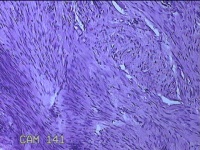

右膝部皮肤肉芽肿

性别

男

年龄

13岁

临床诊断

一般病史

外伤后,出现右膝部皮肤肉芽肿形成。

标本名称

大体所见

灰白暗红色带皮肤样组织2.8x1.8x1.3cm一块,表面糜烂,切面灰白粉红色,质软。